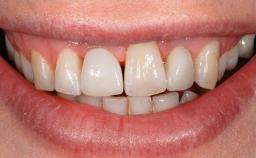

In 2004, the patient, a smoker, began dental treatment at the ACTA graduate clinic. She was a TV producer exposed to a lot of stress in her job and had a sick husband. Her maxillary teeth had been extracted, as had the mandibular canines, premolars, and molars, with the exception of tooth 34. She received a complete maxillary denture and a mandibular skeleton denture. In October 2007, her maxilla was augmented by an oral and maxillofacial surgeon; in March 2008, implants (Biomet 3i, Palm Beach, Florida, USA) were inserted at that same clinic. In 2008, the patient was presented at the Department of Oral Implantology and Prosthetic Dentistry to request restorations for her implants. An implant-supported overdenture was planned. She also asked if we could restore her occlusion with fixed prosthetics.

| Patient's Esthetic Expectations | Low | Medium | High |

| Lip Line | No exposure of papillae | Exposure of papillae | Full exposure of mucosa margin |